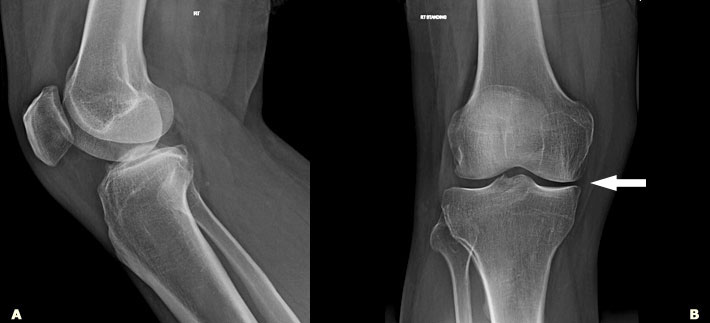

腺甘酸诱发骨头细胞。UC San Diego Jacobs School of Engineering.